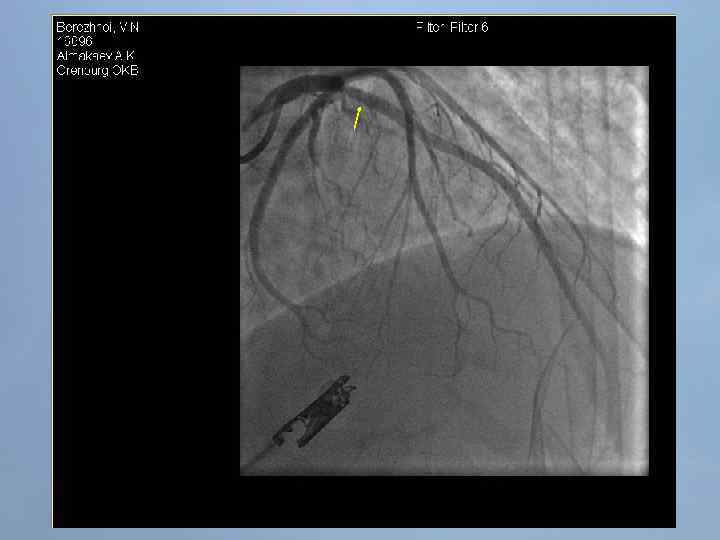

Пациент Б. , 54 года 29. 08. 13 около 10: 00, находясь на рабочем месте, почувствовал боль в груди. После 2 -ух приемов нитроспрея боль не уменьшилась, вызвал СМП. В 10: 20 первой бригадой СМП зафиксирован подъем ST на ЭКГ, начата ТЛТ, вызвана реанимационная бригада. В 10: 50 на месте вызова в присутствии реаниматолога у пациента развивается остановка кровообращения по типу фибрилляции желудочков. Выполнялась СЛР с непрямым массажем сердца, ИВЛ мехом, дефибрилляцией. В течение транспортировки фибрилляция рецидивировала еще 4 раза. Пациент доставлен в ООКБ в 11: 30, минуя приемное отделение госпитализирован в ОРИТ ОИМ.

Проведенные мероприятия: Обезболивание – морфин 1%-1 мл; Введена полная доза пуролазы – 6 млн МЕ; Дана нагрузочная доза клопидогрела - 300 мг; Начата в/в инфузия гепарина – 1000 МЕ/час; Дофамин 4% - в/в через ДЛВ; С противоаритмической целью: Кордарон 300 мг болюсом, затем 600 мг – капельно; Лидокаин 120 мг в/в; Магния сульфат 25% - 15 мл в/в; Калия хлорид 5% - 10 мл в/в.